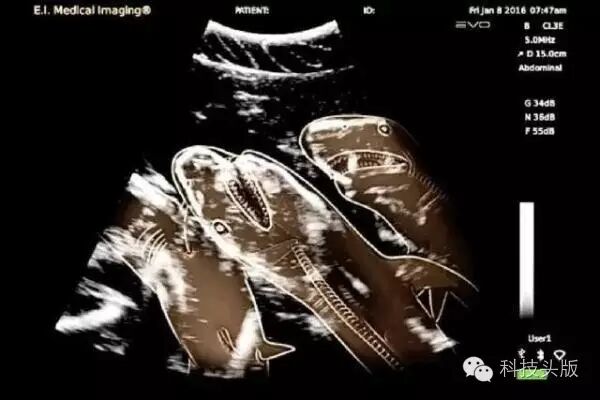

据称这是怀孕的虎鲨,另类而让人瞩目的存在。资料显示,虎鲨宝宝明明是卵生非胎生,那么图中这个一定是鲨鱼宝宝还在蛋壳里还没产出来的样子……